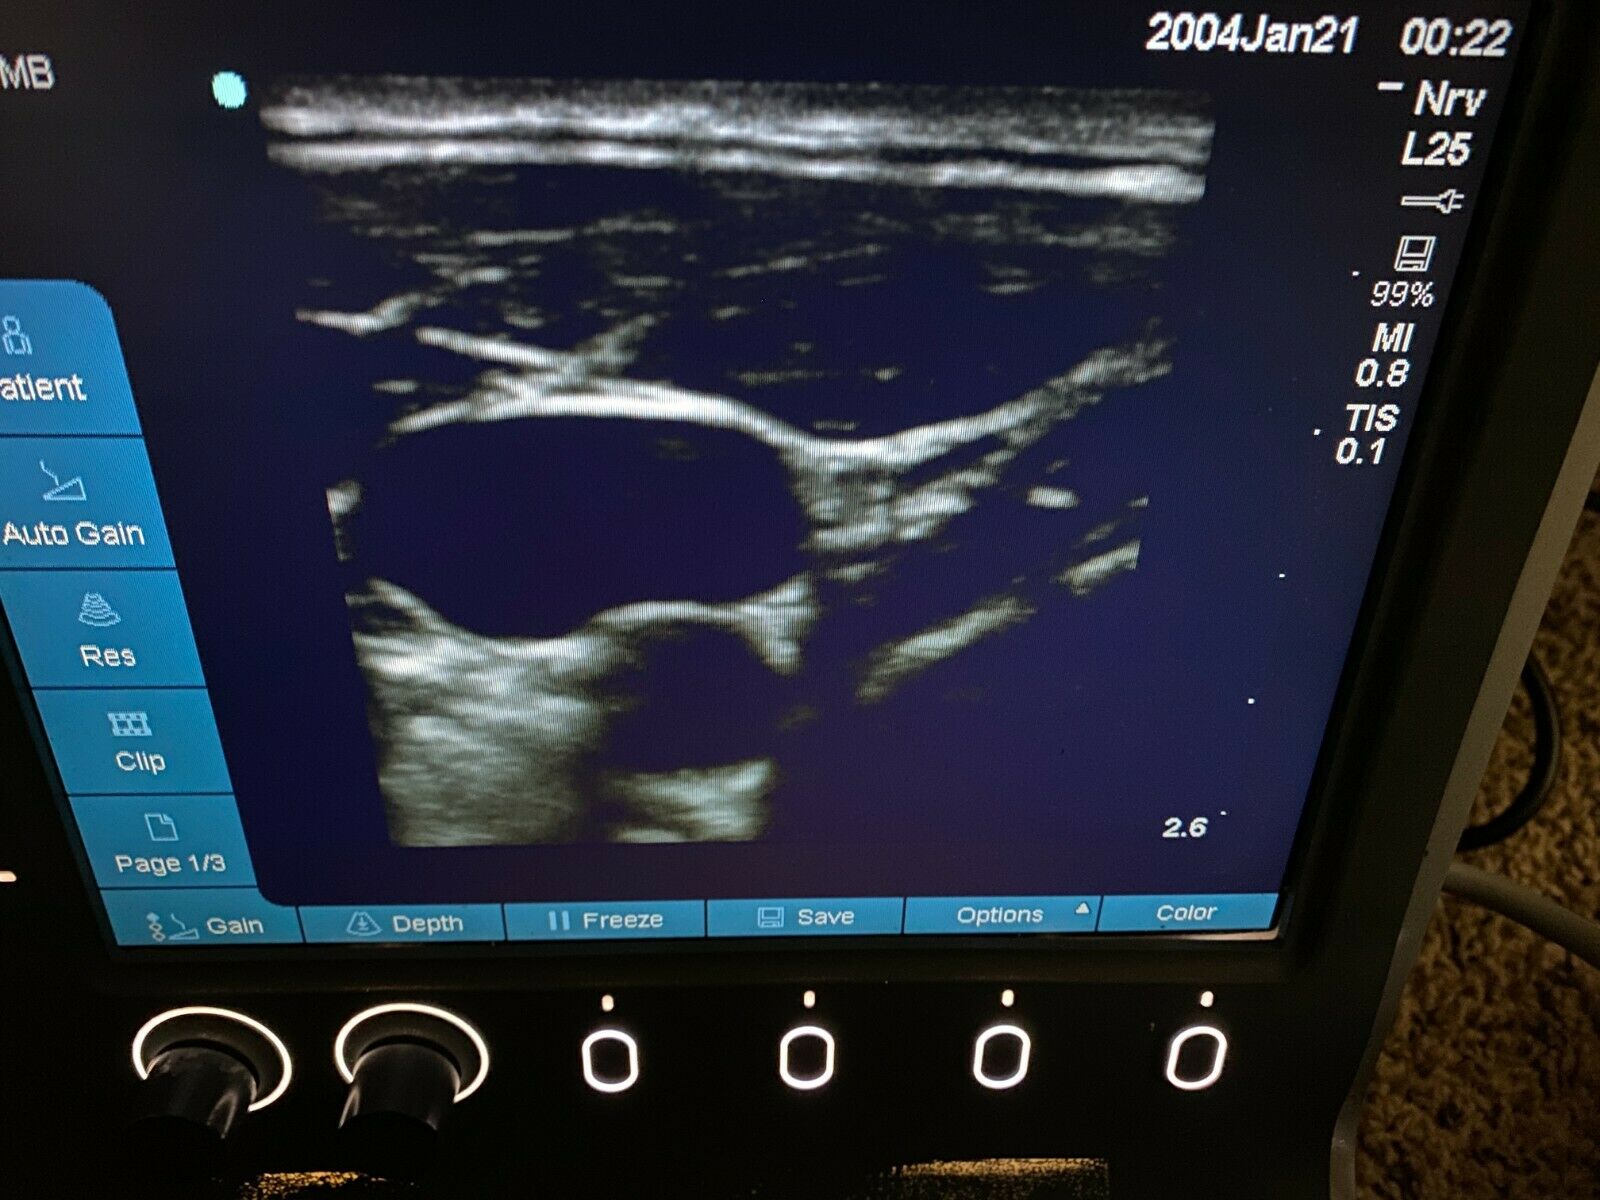

The SONOSITE L25X LINEAR FOR M-TURBO EDGE S is a premier ultrasound transducer designed to provide high-quality imaging for a variety of clinical applications. This specialized probe is compatible with the SONOSITE M-TURBO EDGE system, a leading point-of-care ultrasound device that delivers exceptional image clarity and reliability. Whether you are in emergency medicine, regional anesthesia, or vascular procedures, the SONOSITE L25X LINEAR provides precise and reliable results every time.

Designed with advanced technology, the SONOSITE L25X LINEAR FOR M-TURBO EDGE S offers a frequency range that is optimal for superficial imaging, aiding healthcare professionals in obtaining detailed and accurate images. The probe's ergonomic design ensures ease of use during extended scanning sessions, reducing operator fatigue. SONOSITE, a brand known for its innovation and quality, ensures that every detail of the L25X LINEAR is tailored to meet the high demands of modern medical environments.